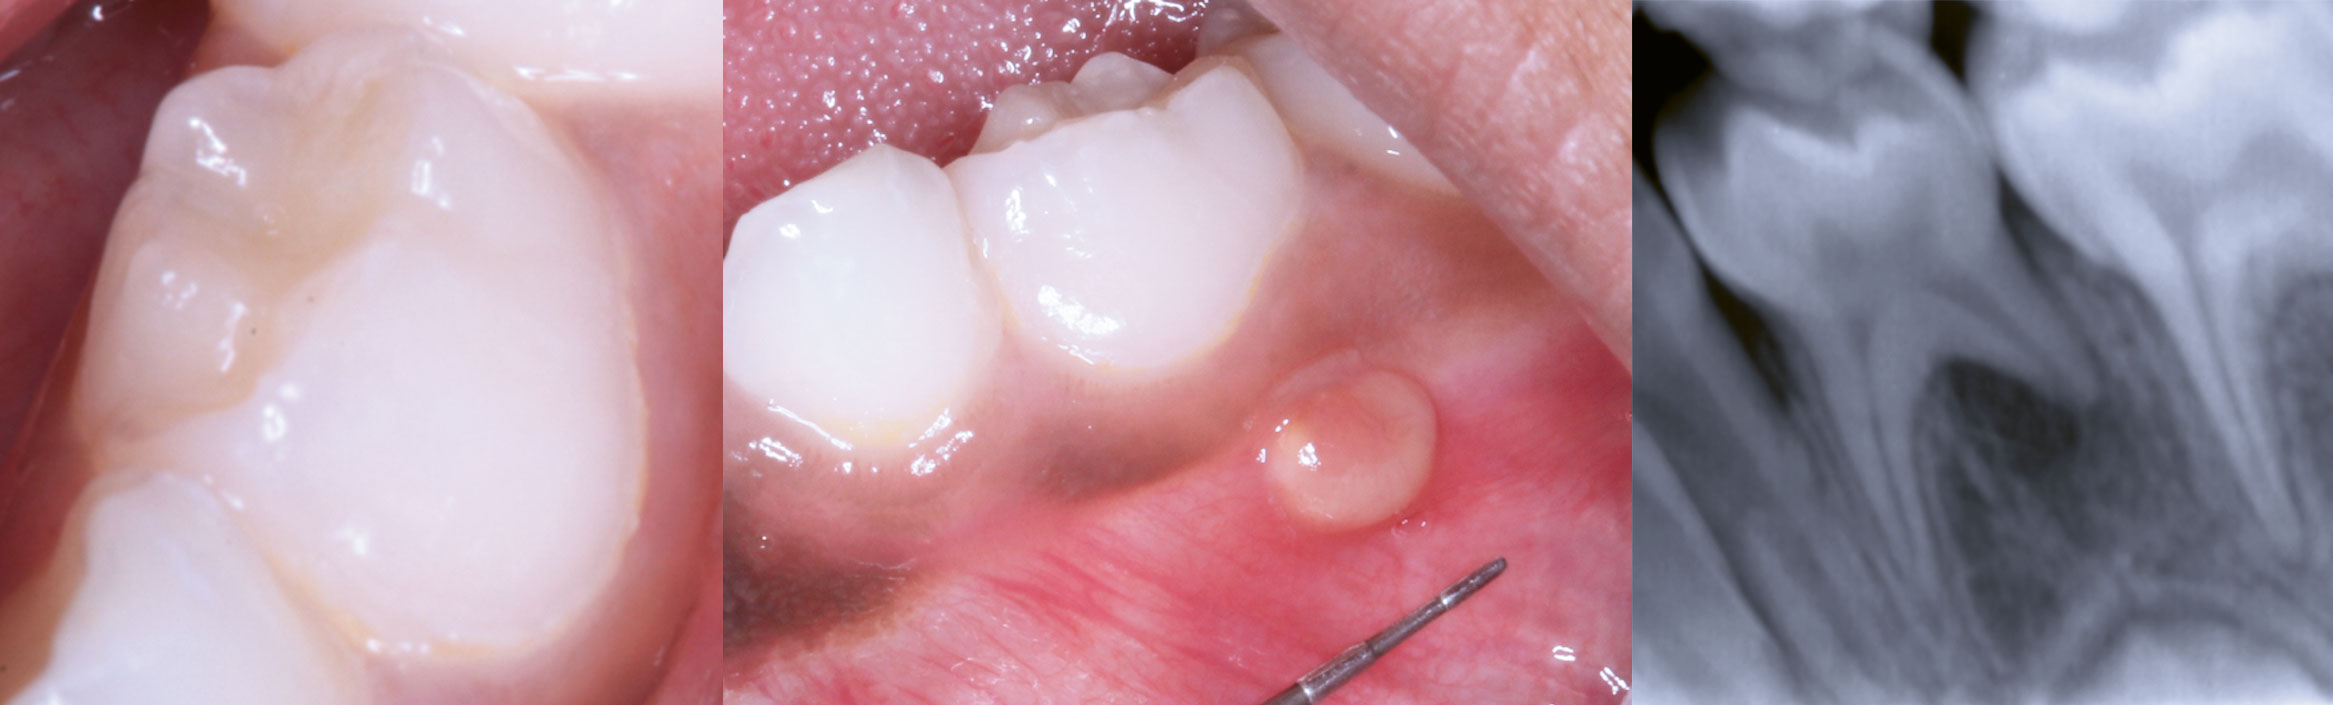

En syv år gammel jente av afrikansk opprinnelse møtte på Klinikk for allmenn odontologi – barn ved Institutt for klinisk odontologi, Universitetet i Oslo, for utredning av en asymptomatisk hevelse bukkalt for lett perkusjonsøm tann 74 (figur 1). Pasienten var ellers frisk og brukte ingen medikamenter. Klinisk undersøkelse viste en hevelse som var gulhvit i farge med glatt overflate, målte 4 mm i diameter og hadde gradvis økt i størrelse den siste måneden. Det var ingen synlig karies eller defekter i kronen til tann 74. Periapikalt røntgenbilde viste diffus periapikal osteolyse langs en kort distal rot, ellers upåfallende tann (figur 1). Kronisk idiopatisk periapikal abscess ble foreslått som tentativ diagnose.

Figur 1. Kliniske foto og periapikalt røntgenbilde viser tilsynelatende morfologisk normal og intakt krone tann 74 (bilde til venstre og i midten), mukosal hevelse bukkalt (bilde i midten) og periapikal oppklaring ved distale rot (bilde til høyre).